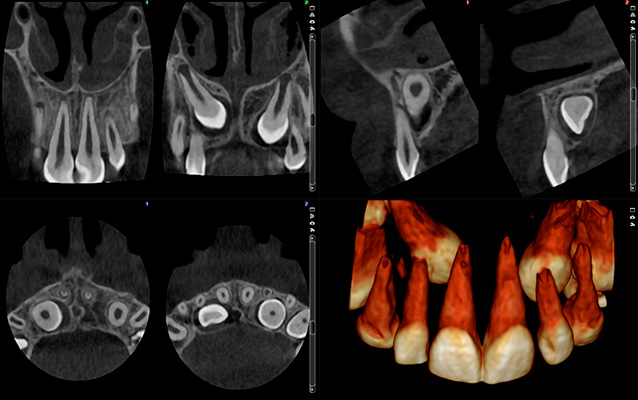

See what you need

High resolutions and standard doses are not always necessary – often less is sufficient. Planmeca Ultra Low Dose 3D imaging is enough to see the mandibular nerve channel for implant planning and wisdom tooth extractions, for example. This can all be done at an incredibly low dose.

HD resolution

voxel size 150 μm, patient dose ~134 μSv

Very much detail, high dose

HD resolution with Ultra Low Dose

voxel size 150 μm, patient dose ~32 μSv

Much detail, low dose

Normal resolution

voxel size 200 μm, patient dose ~86 μSv

Much detail, moderate dose

Normal resolution with Ultra Low Dose

voxel size 200 μm, patient dose ~20 μSv

Much detail, low dose

Low dose resolution

voxel size 400 μm, patient dose ~30 μSv

Less detail, low dose

Low dose resolution with Ultra Low Dose

voxel size 400 μm, patient dose ~6 μSv

Little detail, very low dose